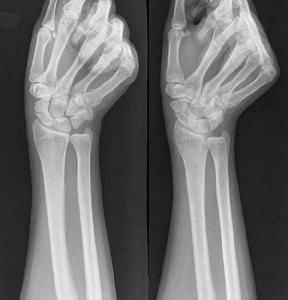

骨性|骨折需要多久能愈合?周期分为这5个阶段,赶紧来学习一下

导语:我们应该都听过这么一句话叫“伤筋动骨一百天”,这是因为一般人发生骨折之后至少需要3个月才能好,所以就有了伤筋动骨一百天这句话。老话自然有它的道理,据现代科学来讲,从发生骨折到愈合大概需要12周的周期,12周左右也就是三个月左右。

骨折愈合周期可分为5个阶段:

【 骨性|骨折需要多久能愈合?周期分为这5个阶段,赶紧来学习一下】1、发生骨折两个周之后,骨痂开始形成,鲜血开始凝块

2、发生骨折一个月之后,会形成骨性骨痂

3、发生骨折8个周之后,骨性骨痂形成已经初步完善

4、发生骨折两个月之后,断裂的骨折部分就已经可以连续起来了,固定的夹板可以去掉

5、发生骨折三个月之后,骨折表面的折线已经修复,差不多就已经愈合了